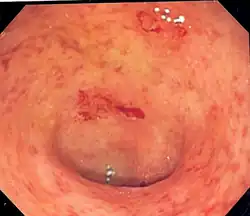

| Endoscopic image of a colon affected by ulcerative colitis. The internal surface of the colon is blotchy and broken in places. Mild-moderate disease. | |

Endoscopic

The best test for the diagnosis of ulcerative colitis remains endoscopy, which is the examination of the internal surface of the bowel using a flexible camera. Initially, a flexible sigmoidoscopy may be completed to establish the diagnosis.[73] The physician may elect to limit the extent of the initial exam if severe colitis is encountered to minimize the risk of perforation of the colon. However, a complete colonoscopy with entry into the terminal ileum should be performed to rule out Crohn's disease and assess the extent and severity of the disease.[73] Endoscopic findings in ulcerative colitis include: erythema (redness of the mucosa), friability of the mucosa, superficial ulceration, and loss of the vascular appearance of the colon. When present, ulcerations may be confluent. Pseudopolyps may be observed.[74]

Ulcerative colitis is usually continuous from the rectum, with the rectum almost universally involved. Perianal disease is rare. The degree of involvement endoscopically ranges from proctitis (rectal inflammation) to left-sided colitis (extending to the descending colon) to extensive colitis (extending proximal to the descending colon).[14]